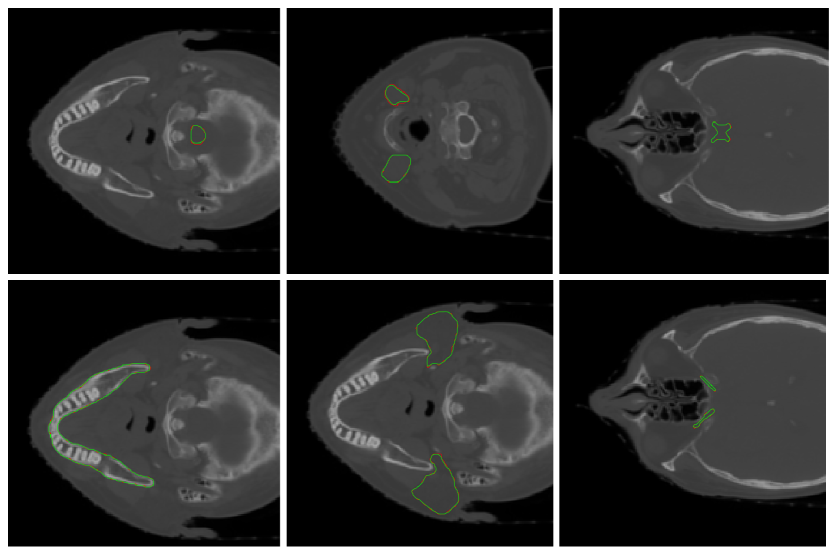

Refer to caption

Figure 4: Performance of segmentation model trained using BSDsubscriptBSD\mathcal{L}_{\mathrm{BSD}} loss function (5) on individual OARs.

We first demonstrate the performance of the models on the case of optic nerves, optic chiasm, and brain stem segmentation. On other structures, the difference between performance of models trained with different loss functions is less significant. The results in terms of Dice coefficient (measure of segmentation quality on which the loss function is based) are shown in Figure 3. Superiority of soft Dice-trained models can be observed. However, standard soft Dice-trained model reaches a significantly smaller precision in case of optic nerves and sometimes misses the structure altogether as also illustrated by Figure 1. The model trained using the proposed batch soft Dice loss does not seem to suffer from this issue and we therefore conclude that it is more suitable for training models for segmentation of small anatomical structures with low contrast such as head and neck OAR.

Figure 5: Examples of successful segmentation outputs (green) with corresponding ground truth annotations (red). Upper row from left to right: brain stem, submandibular glands, optic chiasm, lower row from left to right: mandible, parotid glands, optic nerves.

The overall performance of our model for each individual OAR is shown in Figure 4. Specific examples of successful segmentation for each tissue is shown in Figure 5. Except for several outlier cases where optic nerve segmentation reached a lower precision with the Dice coefficient around 0.60.60.6, we obtained acceptable results with Dice coefficient over 0.80.80.8 for all structures. We quantitatively compare our method with other published methods in terms of Dice coefficient (Table 1) and in terms of average surface distance [16] (Table 2). Although the difference is most accentuated in cases of optic nerves and chiasm segmentation, our model also surpasses current state-of-the-art results on all the remaining OARs.